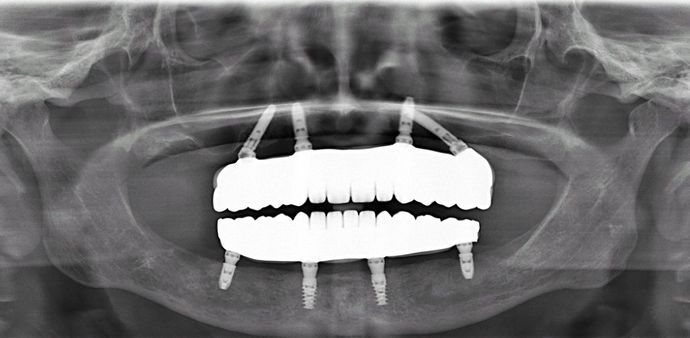

All-on-4/ Full Mouth Dental Implants / Teeth in a Day: Case 1-WG- Upper and lower All-on-4 bridges

Procedures : extractions, implants, All on 4 , Teeth in a day, no bone grafting and full mouth reconstruction with monolithic zirconia bridges.